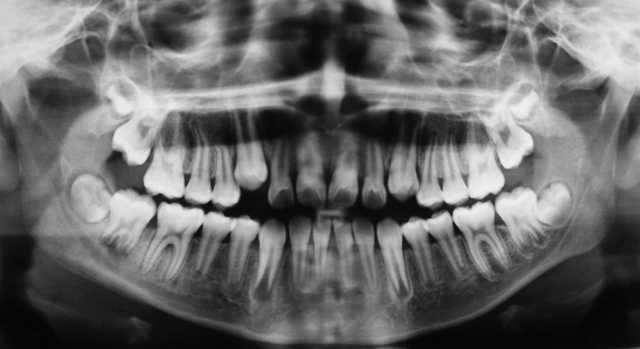

Otto Walkhoffek, Braunschweigen, lehenengo hortz-radiografia egin zuen,

Tutu katodikoekin lanean ari zelarik erradiazio mota berri hau aurkitu zuen, geroago hainbesteko garrantzia izango zuena. Eponimo guztiei uko egin zien eta ez zuen bere aurkipena patentatu uste baitzuen zientzia ez zela dirua egiteko tresna bat. X izena jarri zien berarentzat izaera misteriotsua baitzeukaten, algebran ezezagunari jarritako hizpiari erreferentzia eginez.